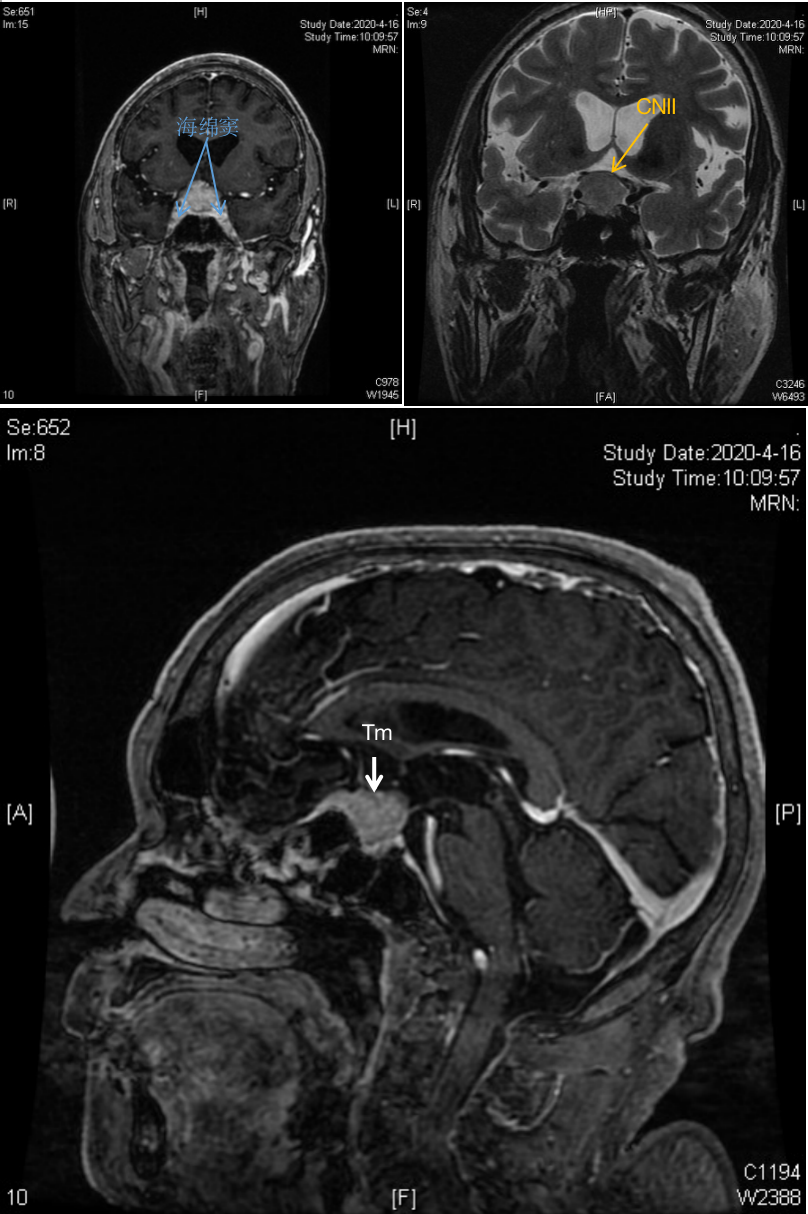

核磁共振所见:

鞍区见不规则异常信号影,大小约34*28*30mm,有明显强化,肿瘤上方抵近大脑前动脉及前交通动脉复合体,右侧包裹颈内动脉。肿瘤向右上方生长,已突破鞍隔,并向右上方压迫视交叉。